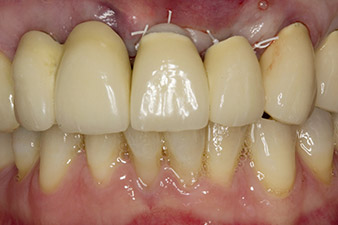

Situation following implantation

Fig. 6: Situation following implantation and augmentation: The old bridge was reinserted as a temporary restoration for the healing phase with a freely milled pontic at implant position 22. The planned permanent restoration will be a zirconium oxide bridge from 12 to the implant yet to be inserted at position 23.